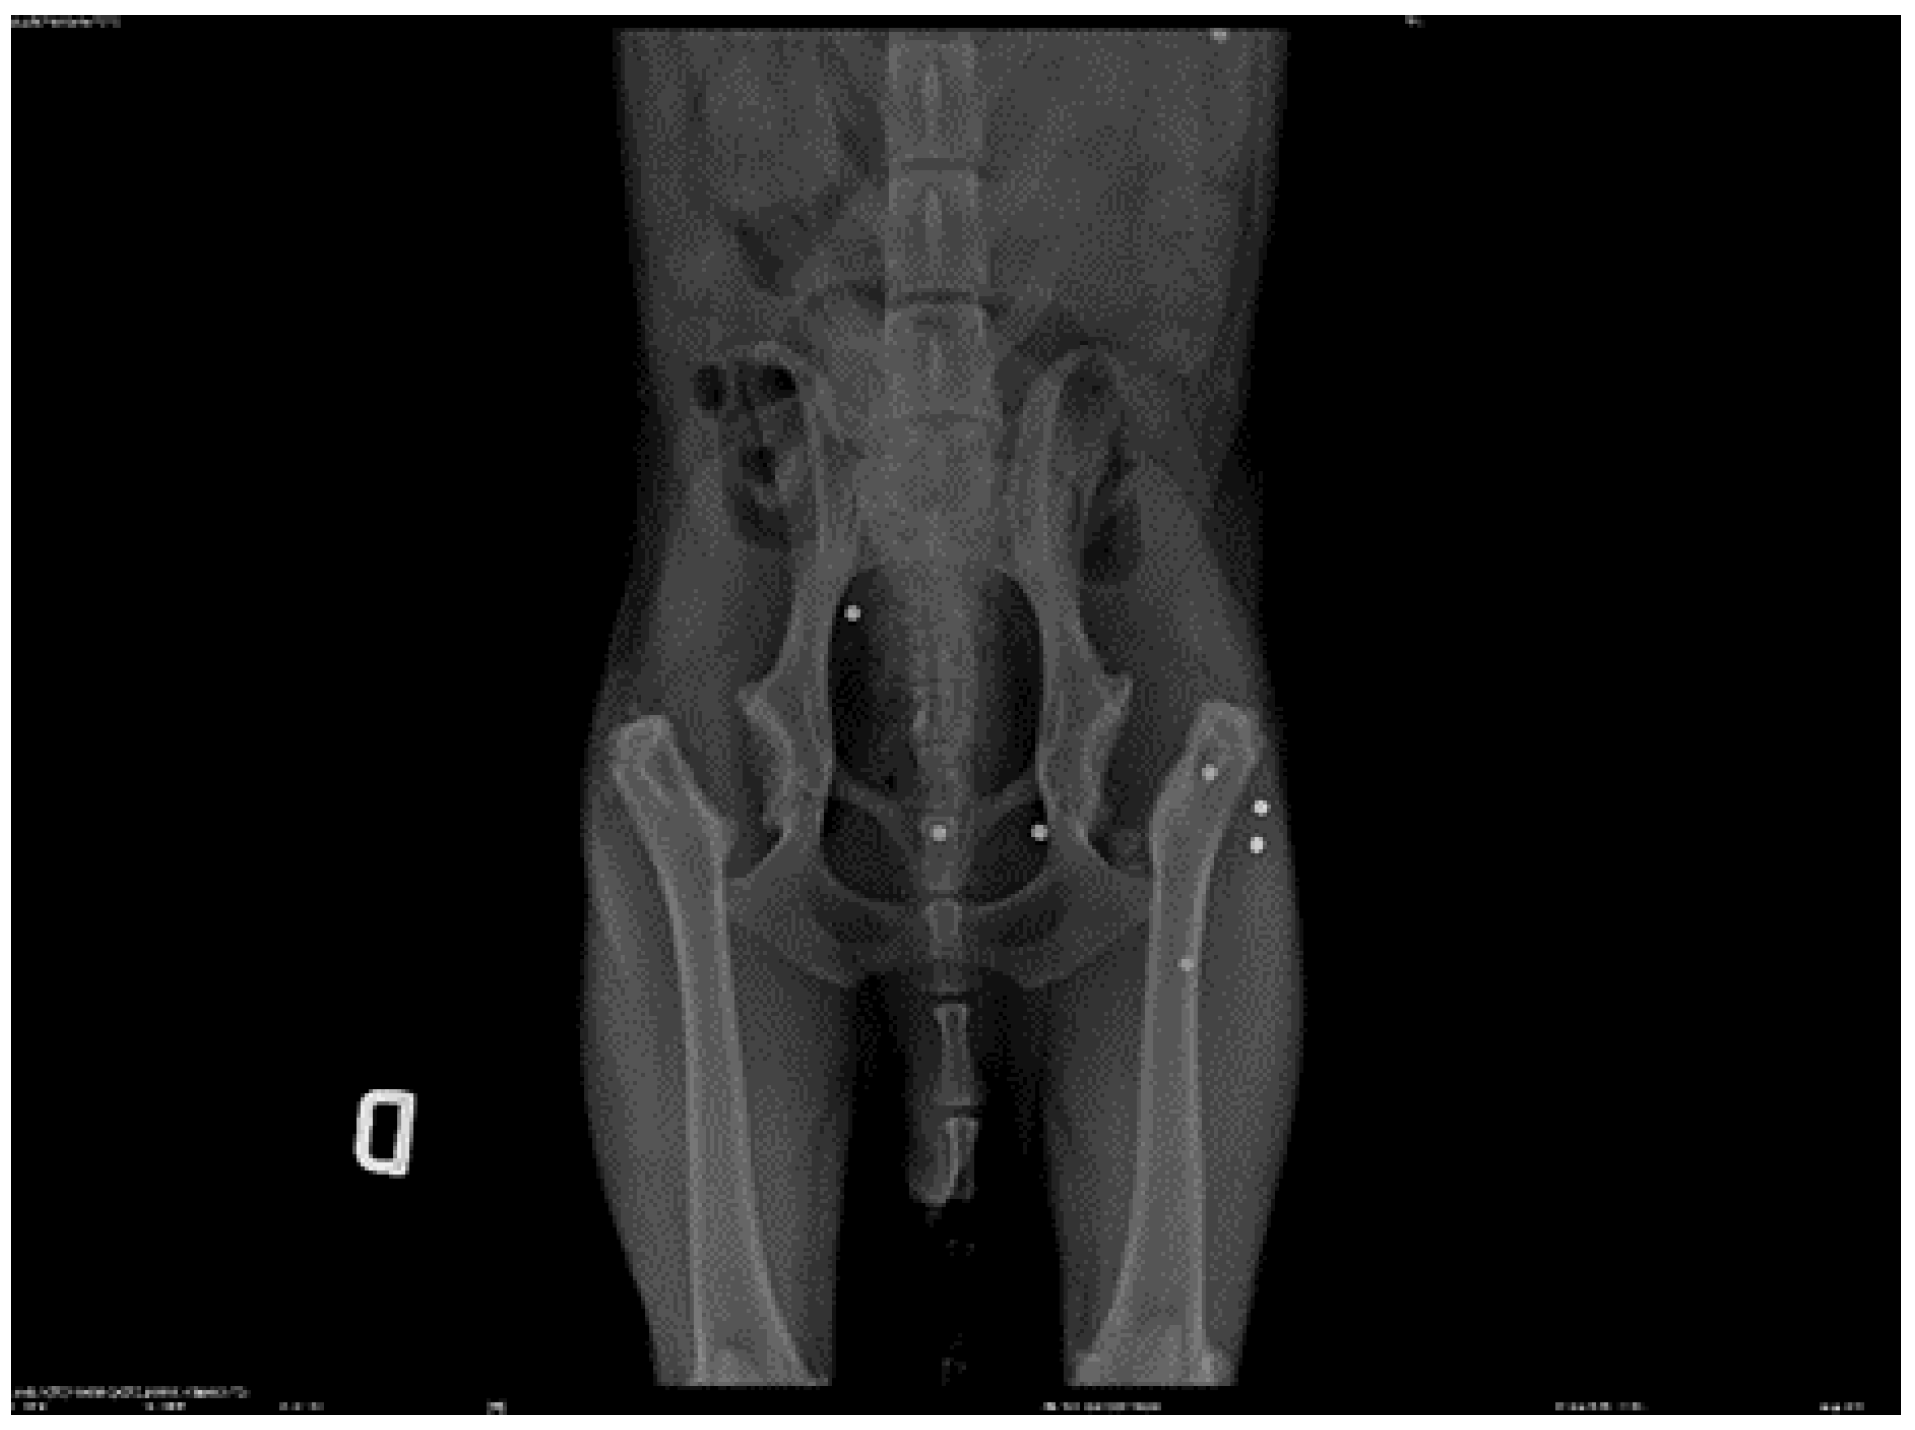

![]() |